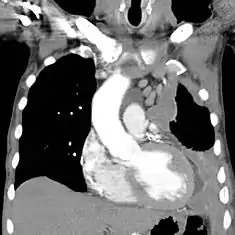

![]() | |

| سیتی اسکن showing a left sided mesothelioma with an enlarged mediastinal غدد لنفاوی | |